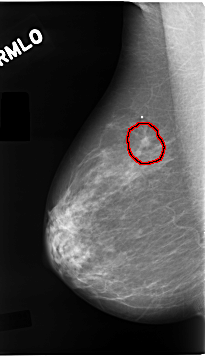

C_0096_1.RIGHT_MLO

RIGHT_MLO LINES 4672 PIXELS_PER_LINE 2656 BITS_PER_PIXEL 12 RESOLUTION 50 OVERLAY

FILE: C_0096_1.RIGHT_MLO.OVERLAY

TOTAL_ABNORMALITIES 1

ABNORMALITY 1

LESION_TYPE CALCIFICATION TYPE PLEOMORPHIC DISTRIBUTION CLUSTERED

LESION_TYPE MASS SHAPE IRREGULAR MARGINS SPICULATED

ASSESSMENT 5

SUBTLETY 5

PATHOLOGY MALIGNANT

TOTAL_OUTLINES 1

BOUNDARY